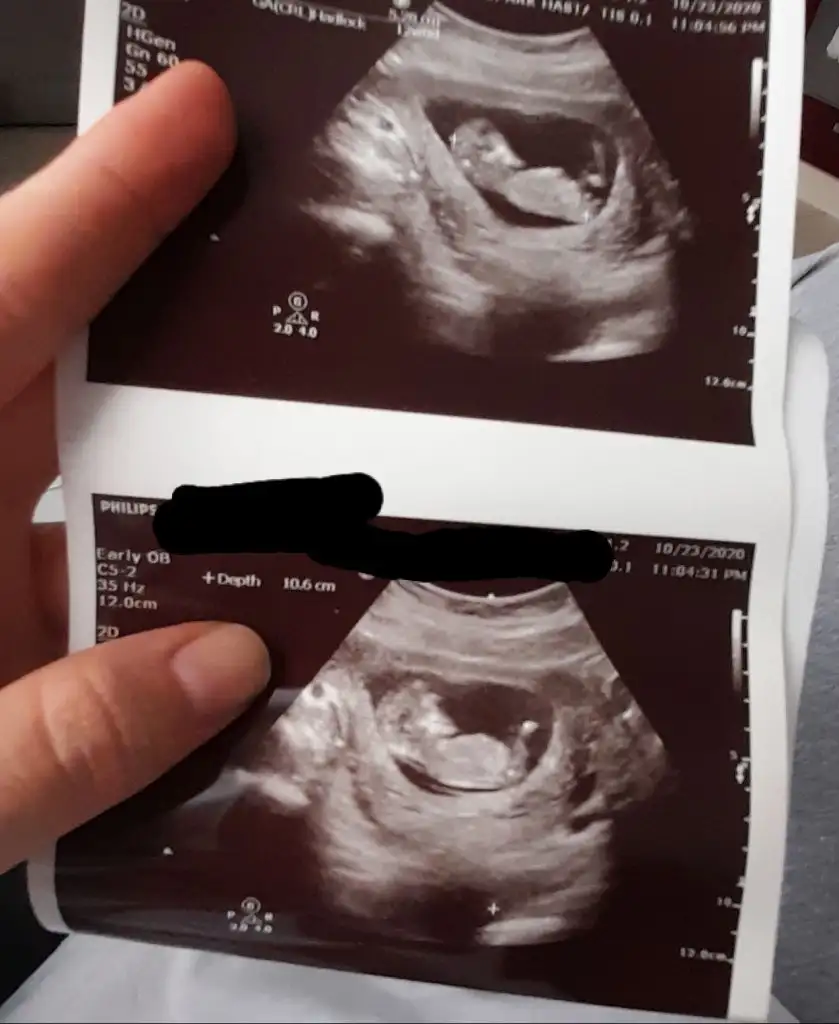

Kıza benzettimEki Görüntüle 2710264 banada tahmin yaparmisiniz lütfen

banada tahmin yapabilir misiniz 12haftalik

Bence kız gibibanada tahmin yapabilir misiniz 12haftalik

Eki Görüntüle 2710264 banada tahmin yaparmisiniz lütfen

Canım senin bebiş erkeğe benziyorEki Görüntüle 2710264 banada tahmin yaparmisiniz lütfen

Erkek gibi sanki eninde olamadim çok karanlık nubu sanki biraz bir diklik var umarım u nubturIkra meyra 12+1 iz bize de tahmin de bulunabilir misiniz